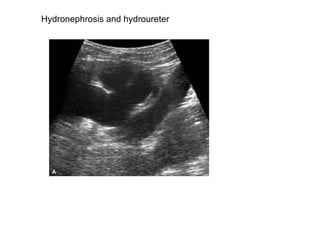

Hydronephrosis and hydroureter

Hydro nephrosis and hydro ureter